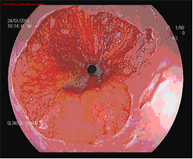

Diagnosis is performed using high-resolution magnification endoscopy (image enhancement), employing additional chromoendoscopy techniques conducted by endoscopists specialised in the early diagnosis of premalignant lesions, with targeted biopsies for analysis.

The HALO radiofrequency ablation system safely and uniformly ablates the oesophageal mucosa to a depth of approximately 1 mm. Ablation is a technique in which tissue is heated until it is no longer viable or alive. HALO technology is a very specific type of ablation where heat energy is applied precisely and in a controlled manner. Clinical trials have demonstrated that Barrett's tissue can be completely eliminated with HALO ablation technology in 98.4% of patients.